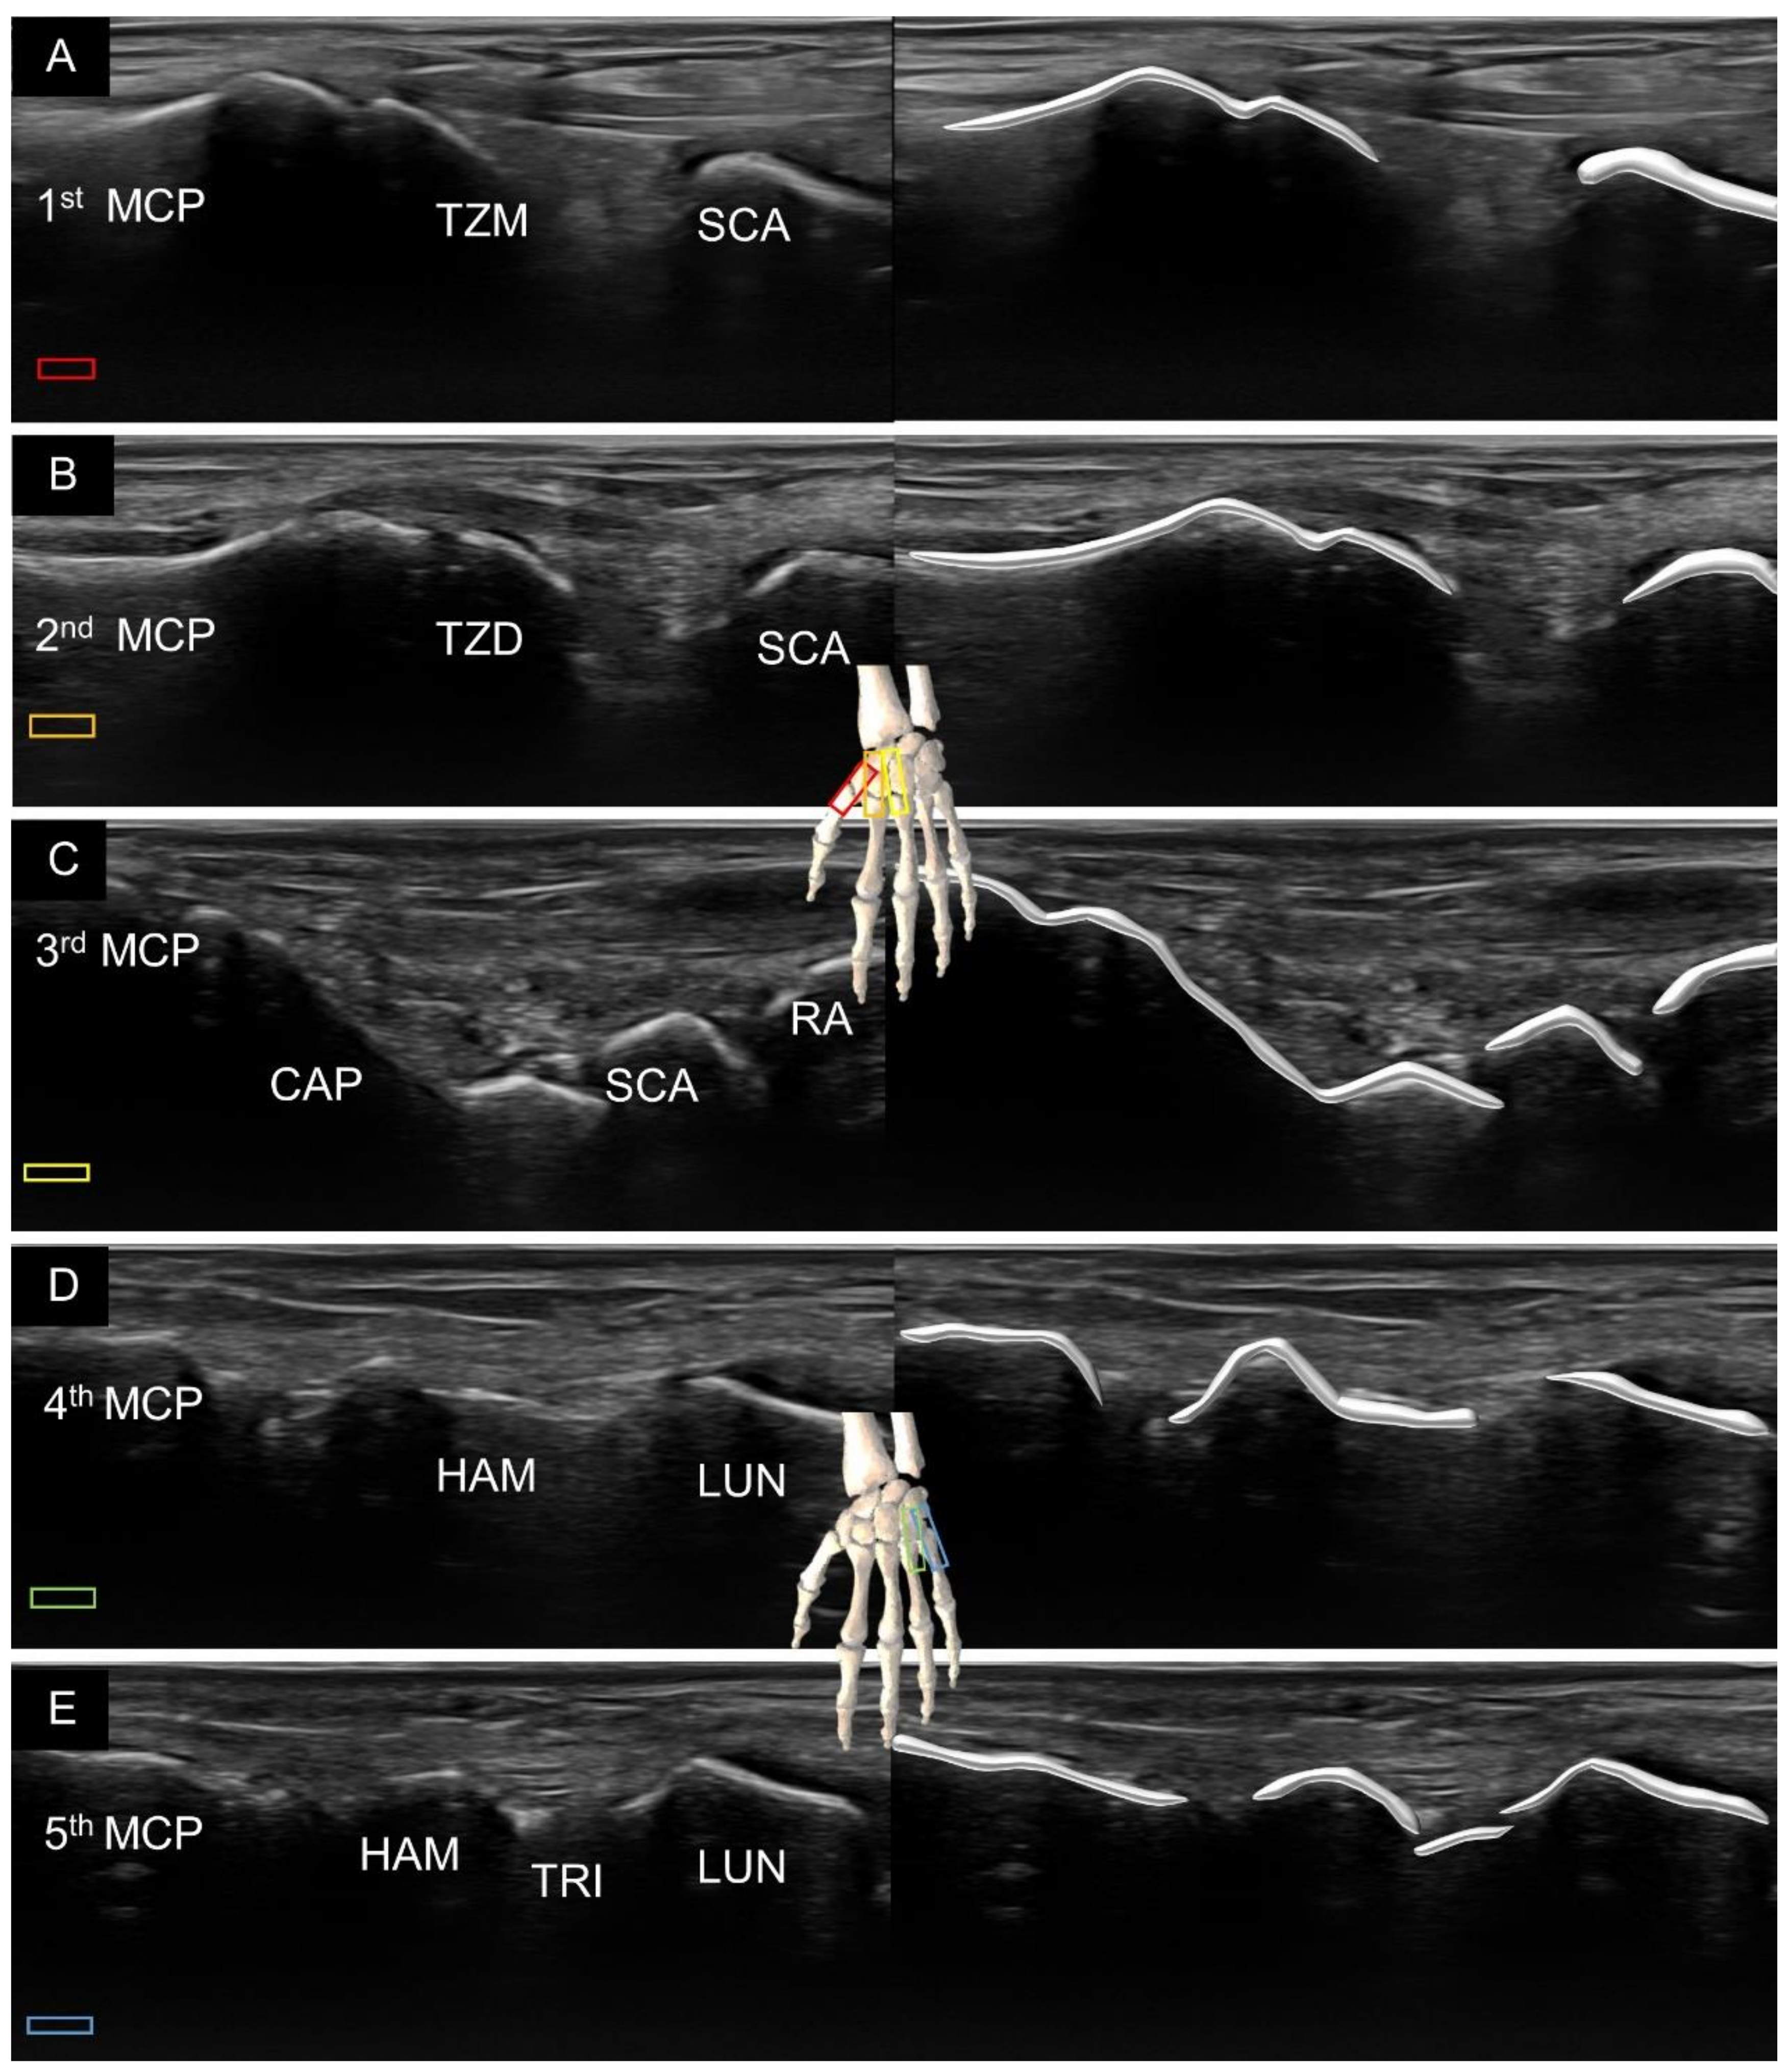

2. Sonoanatomy of Carpal Bones

7. Sonoanatomy of Wrist Collateral Ligaments